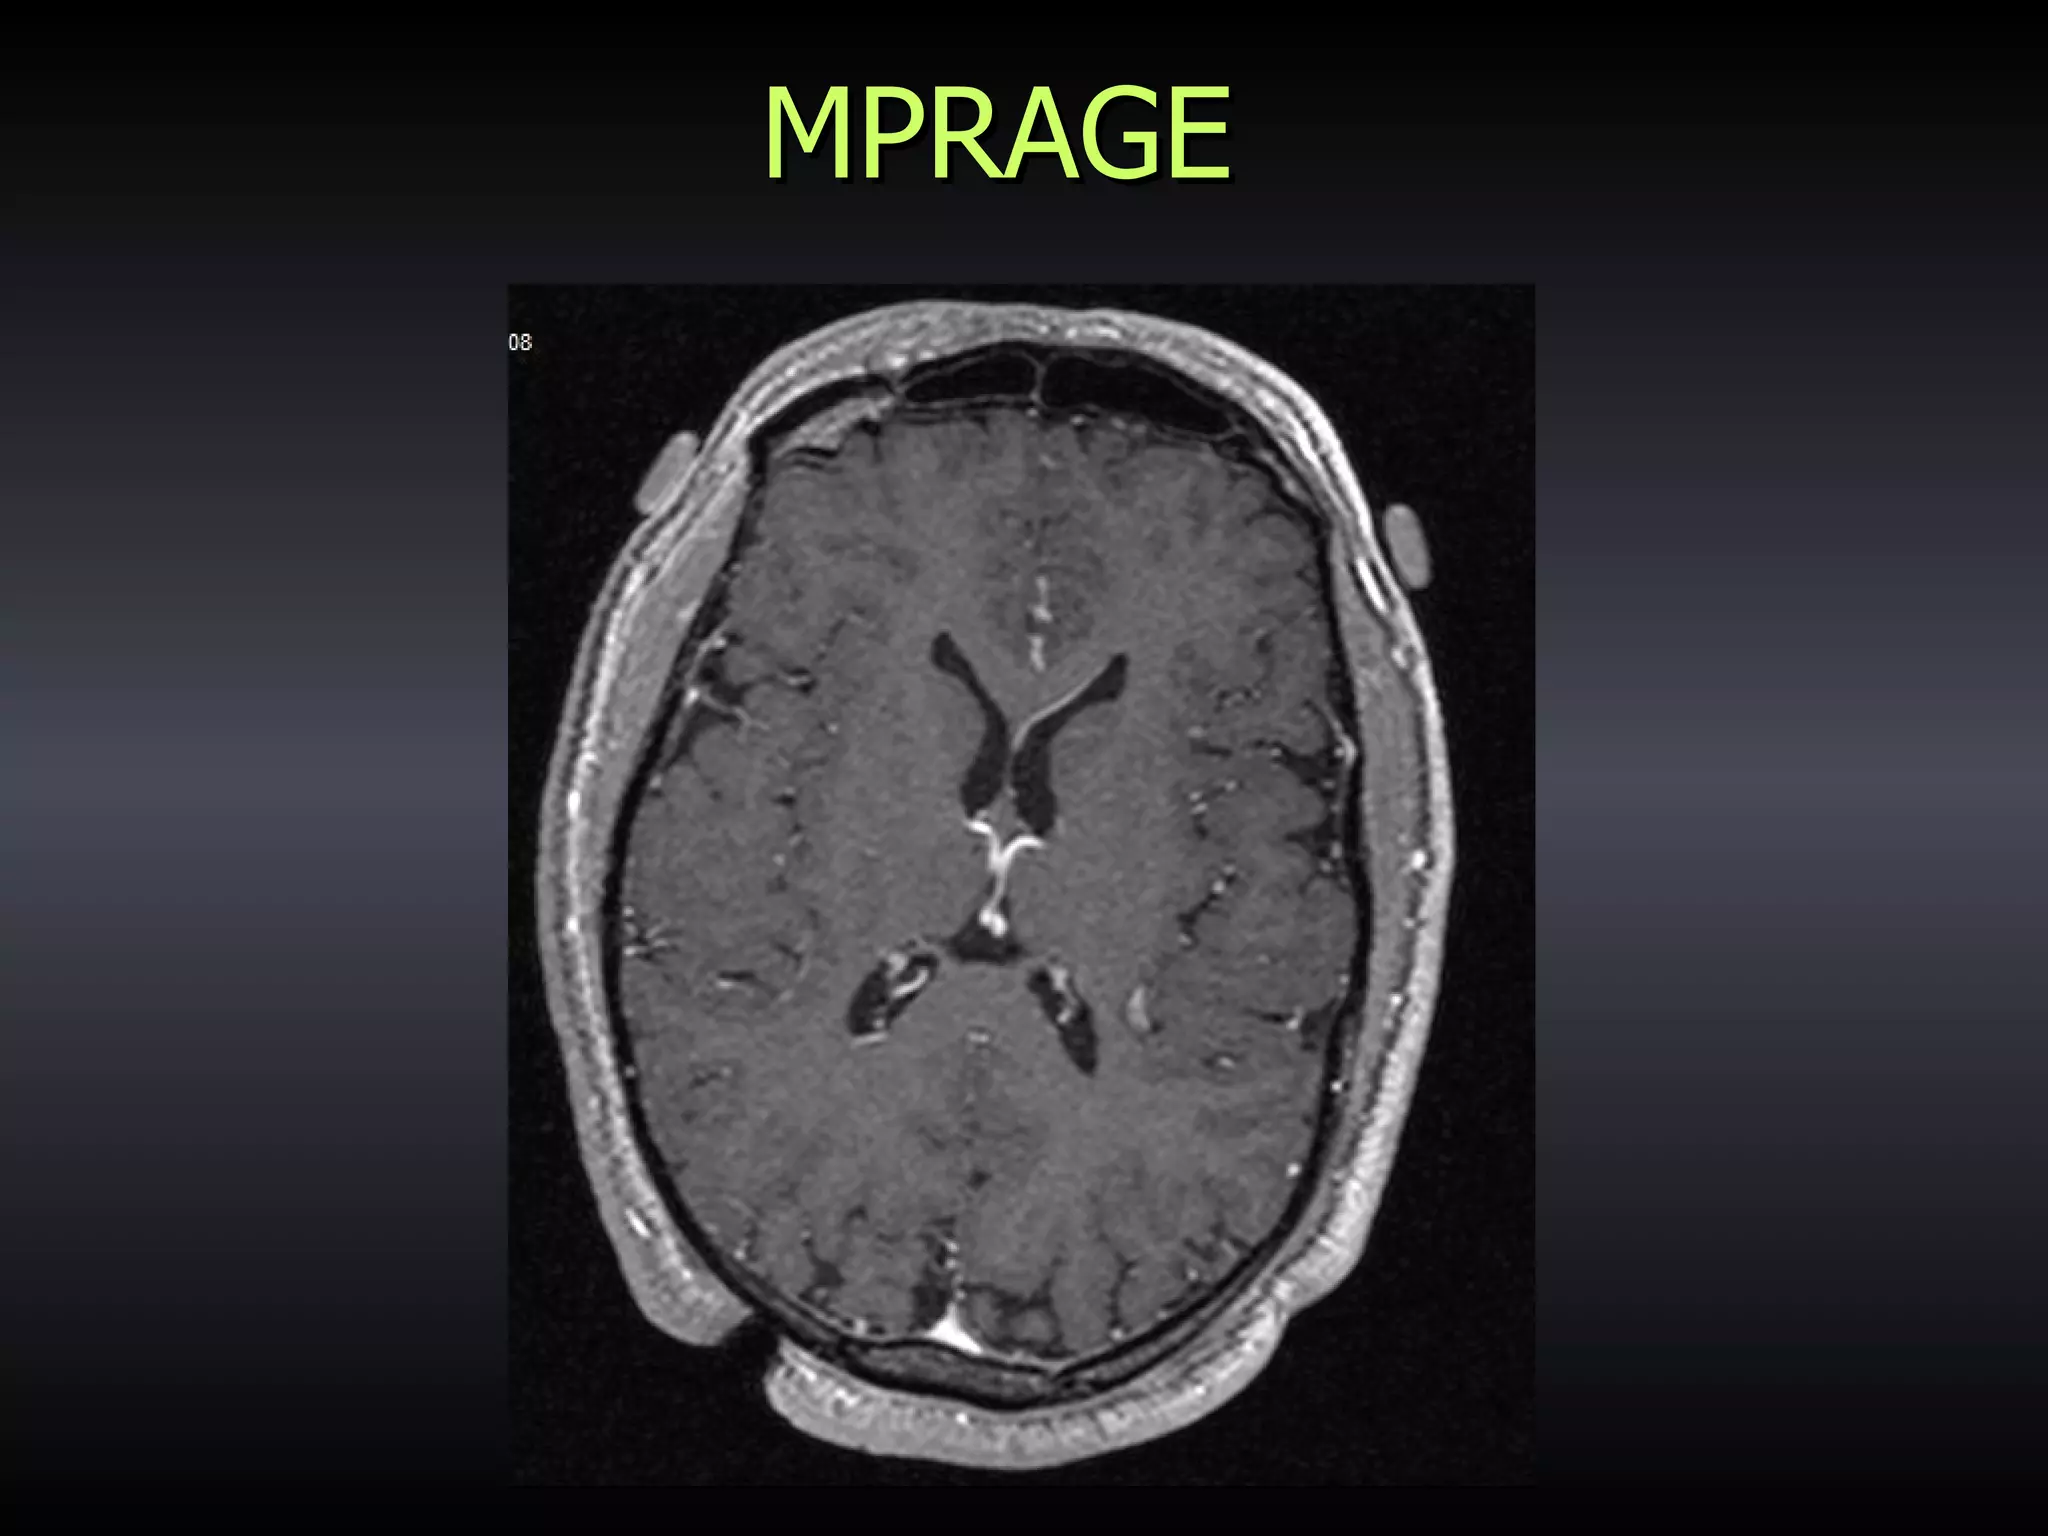

MPRAGE

TECHNIQUE Image Guidance in Trans-sphenoidal surgery

TECHNIQUE